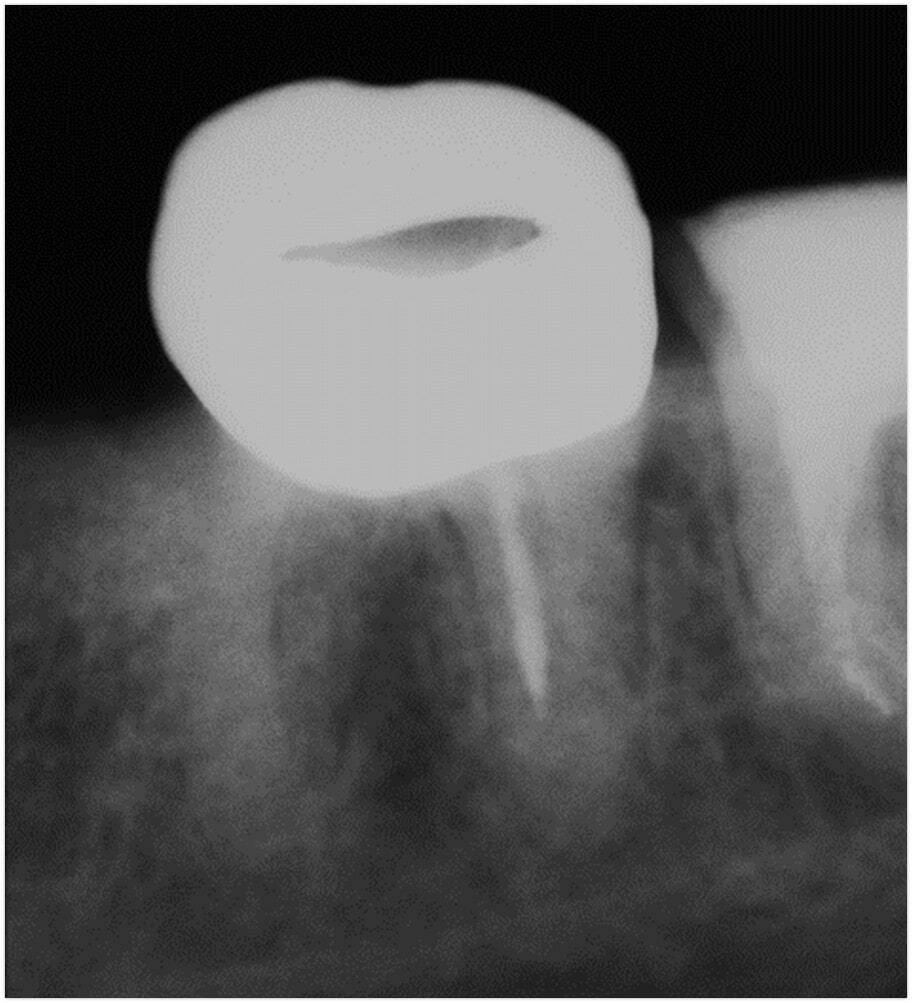

• Діагностика можливості проходження за допомогою кт та інтраоральних знімків